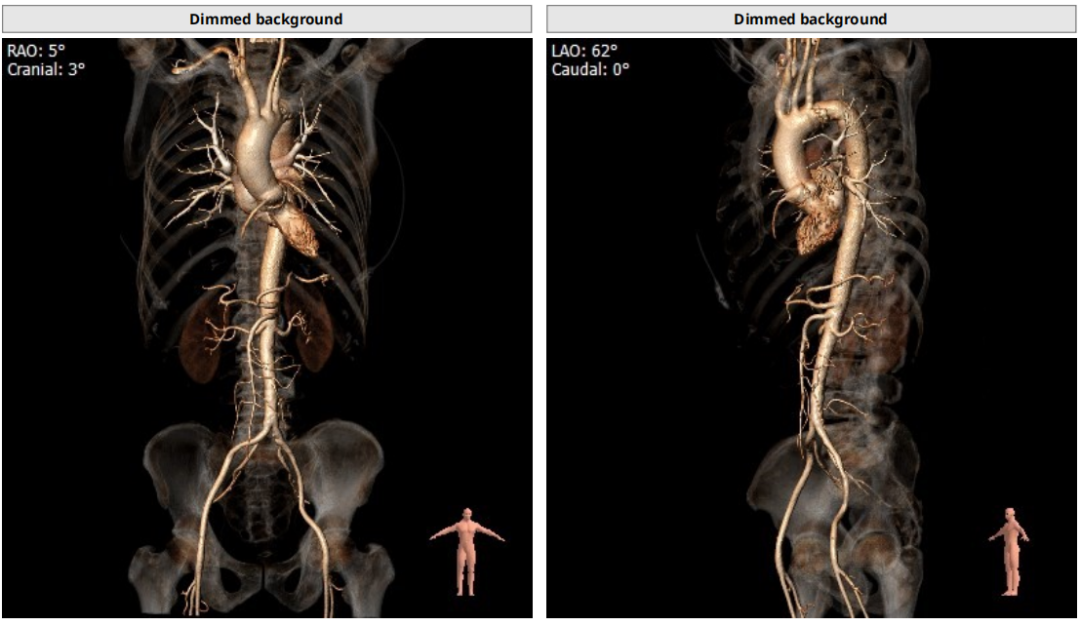

type1型二叶瓣,重度钙化

钙化主要分布在右冠窦和无冠窦

左冠高度稍低,存在一定冠脉风险

Annulus:25.8mm

LVOT:27.1mm

STJ 30.6mm

升主动脉:38.4mm

LM:10mm

RM:12.2mm

CT分析

以3个窦消失最低点确认的平面作为虚拟瓣环平面初步筛选瓣膜尺寸。自展瓣参考周长得出的Annulus直径,该病人为25.8,根据自膨胀瓣膜特点需要oversize,初步判断为29/32瓣膜。LVOT直径大于Annulus,短径24mm,足够限制瓣膜,提供锚定支撑力。STJ高度足够,可提供足够空间给原有瓣叶,过宽的STJ则无法提供释放中锚定支撑力。

窦部的空间与左右冠脉开口高度结合瓣叶形态,是否增厚可以初步判断瓣叶是否会在瓣膜植入后遮挡冠脉开口造成急性的冠脉堵塞。该病人左冠开口略低,且钙化集中在右冠和无冠窦,判断冠脉风险较高。需术中球扩判断是否进行冠脉保护。

升主动脉未见增宽,心脏角度合适极重度钙化,多集中在基底部位二叶瓣重度钙化THV需要downsize选择26/29瓣膜。

入路:入路观察是否有溃疡、钙化、迂曲、血管狭窄等情况,以判断夹层风险。该病人入路情况良好,优先选择右股作为输送系统主入路。